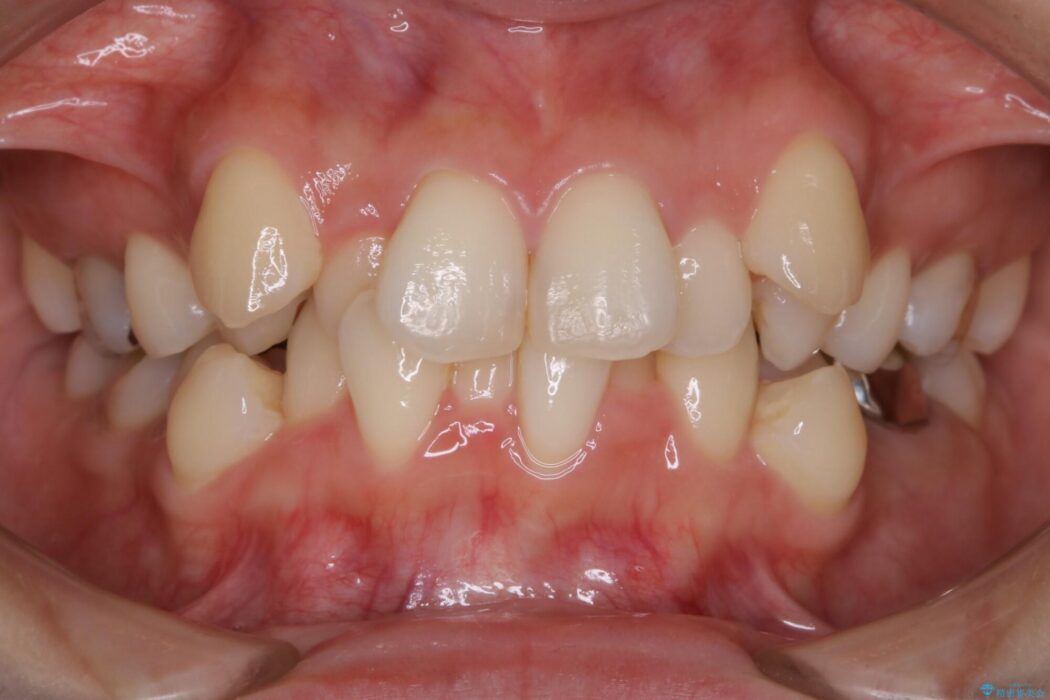

歯列のガタガタと飛び出ている前歯を治したいとのことで来院されました。

目立たない矯正装置をご希望でしたのでマウスピース装置(インビザライン)をご提案しました。

装置の範囲内で可能な限り前歯の位置を動かし整えるため、マイクロインプラントを用いて遠心移動をする歯列矯正を計画しました。

本症例では上顎前突(出っ歯)や歯列のがたつきを改善するスペースを確保するために、歯を遠心移動をサポートすることができるマイクロインプラントを用いたゴムかけを行っていただきました。